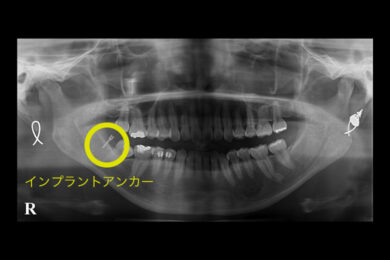

インプラントアンカーを用いたワイヤーによる部分矯正症例

親知らずの前にある奥歯が斜めに生え、年々倒れていくのが心配になり来院されたケースです。

②歯を起こすスペースができたので、顎の骨にインプラントアンカーという小さいネジを埋め込み、倒れた奥歯を繋げて矯正用のゴムで起こしていきます。